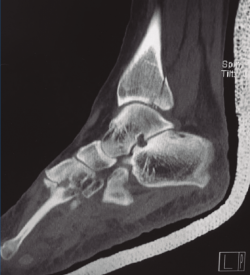

Figura 1. Tomografía computarizada que muestra fractura del maléolo posterior con pequeño fragmento intermedio.

La exploración radiológica comprende las proyecciones AP, de la mortaja y lateral (L). En la proyección AP puede observarse el flake fragment sign o spur sign, que es un doble contorno del maléolo medial, indicativo de fractura del MP con extensión al maléolo interno. La TC es fundamental para reconocer la anatomía del fragmento, su propagación medial, conminución y número de fragmentos intermedios (Figura 1).